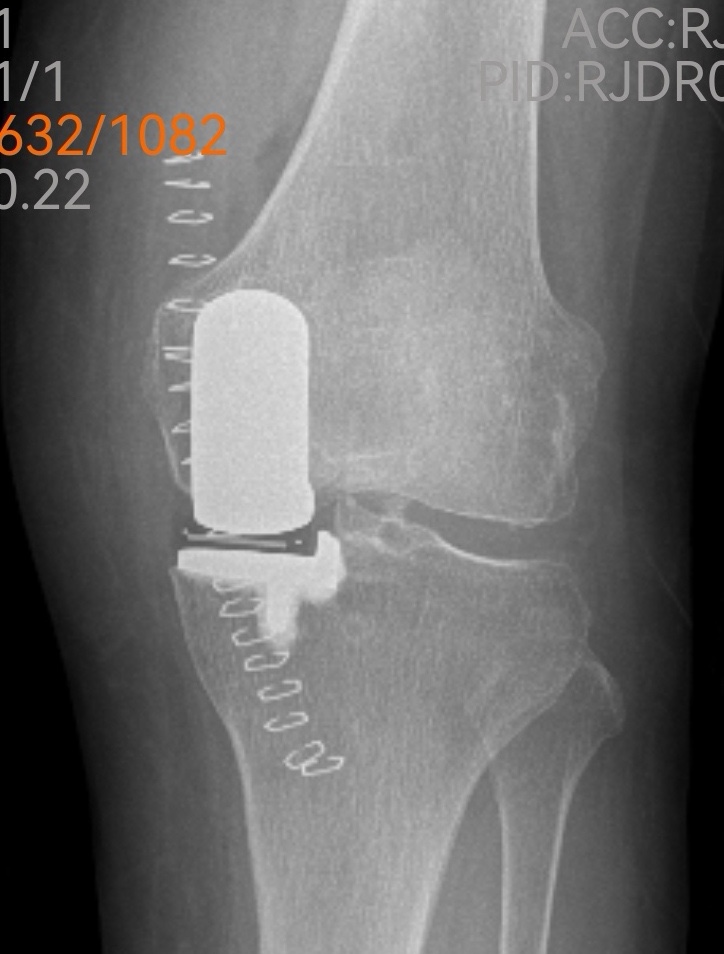

傳統(tǒng)的全膝關(guān)節(jié)置換固然能解決問題,但創(chuàng)傷較大、恢復(fù)期長。經(jīng)過團(tuán)隊(duì)綜合評估,魏海清主任提出了一個(gè)更精細(xì)的方案:“我們建議行左膝關(guān)節(jié)單髁置換術(shù)。這就像牙齒壞了,我們不必把所有牙齒都換掉,而是只替換損壞的部分。這種手術(shù)只替換磨損的軟骨和部分骨質(zhì),能最大限度保留健康組織。”他拿出膝關(guān)節(jié)模型,耐心地向一家人解釋手術(shù)原理:“您看,膝關(guān)節(jié)分為內(nèi)側(cè)、外側(cè)和髕股三個(gè)部分。您的磨損主要集中在內(nèi)側(cè),所以我們只需置換這一部分。”這種個(gè)體化、精準(zhǔn)化的治療理念,讓原本忐忑的一家人逐漸安心。

手術(shù)室里,骨科、麻醉科、手術(shù)室團(tuán)隊(duì)配合默契。微創(chuàng)切口僅有傳統(tǒng)手術(shù)的一半大小,精細(xì)的操作在關(guān)節(jié)鏡輔助下進(jìn)行。沒有大刀闊斧的創(chuàng)傷,只有精準(zhǔn)細(xì)致的重建。一小時(shí)后,手術(shù)順利結(jié)束,出血量僅約100毫升。“這么快?”等候在外的兒子們幾乎不敢相信。魏海清主任走出手術(shù)室,微笑點(diǎn)頭:“很順利,單髁置換本來就是微創(chuàng)手術(shù),對患者損傷小。”

出院前,李阿姨特意換上了從家鄉(xiāng)帶來的紅色外套,與醫(yī)療團(tuán)隊(duì)合影留念。鏡頭前,她的笑容燦爛而真實(shí)。魏海清主任看著這位千里求醫(yī)的患者,心中感慨:“上了年紀(jì)的人最怕關(guān)節(jié)問題導(dǎo)致無法活動(dòng)。長期臥床會(huì)引起一系列并發(fā)癥,嚴(yán)重影響生活質(zhì)量。我們采用的改良微創(chuàng)手術(shù),出血少、損傷小、恢復(fù)快,符合快速康復(fù)理念。”他頓了頓,繼續(xù)說道:“患者跨越兩千多公里選擇我們,這份信任沉甸甸的。作為醫(yī)生,我們唯有以精湛技術(shù)和全心關(guān)懷相回報(bào),才不負(fù)這份生命的托付。”